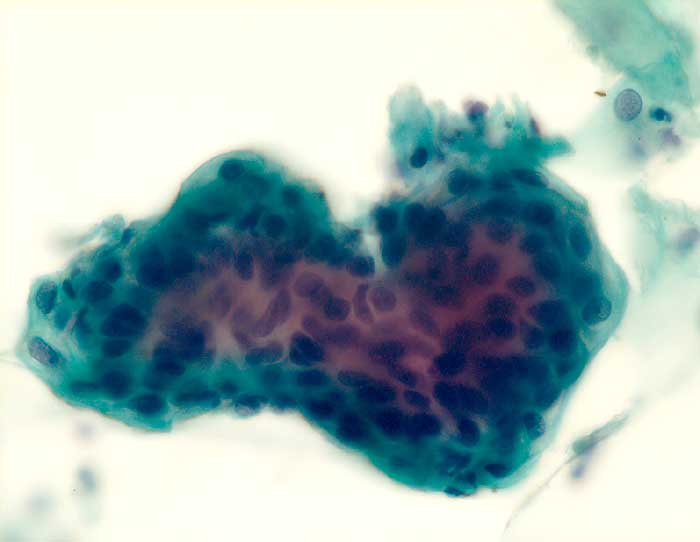

Seröses Adenokarzinom des Endometrium

Die Zellkerne der serösen Adenokarzinome sind in den meisten Fällen hochgradig atypisch. Das Zellbild gleicht entsprechend demjenigen eines wenig differenzierten endometrioiden Adenokarzinoms. Da das seröse Karzinom anders als das endometrioide Karzinom nicht Folge eines Hyperöstrogenismus ist, zeigen die meist postmenopausalen Patientinnen keinen hohen Aufbau des Vaginalepithels im PC-Abstrich.